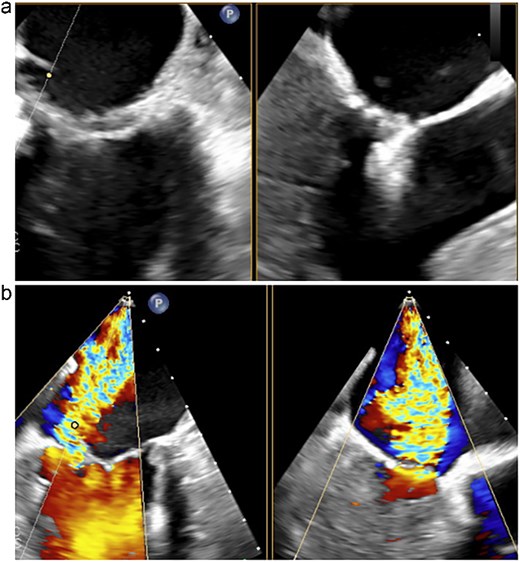

An 80-year-old woman with a history of chronic kidney disease, ulcerative colitis, and dyslipidemia had been followed for severe MR for the past 6 years. She presented with progressive dyspnea and was admitted with acute decompensated heart failure. Transthoracic echocardiography (TTE) demonstrated significant prolapse of the A3 segment and a markedly reduced left ventricular ejection fraction (LVEF) of 30%. Given her frailty, impaired ventricular function, and multiple comorbidities, conventional surgical mitral valve repair was deemed high risk. Therefore, the MitraClip system was selected and performed by the cardiology team. During the MitraClip procedure, however, a posterior mitral leaflet tear occurred, resulting in worsened severe MR (Fig. 1). Consequently, the patient was referred to our department for operation.

Transesophageal echocardiography following the MitraClip procedure. (a) The posterior mitral leaflet is torn, resulting in a loss of continuity. (b) Mitral regurgitation is observed originating from the site of the tear.